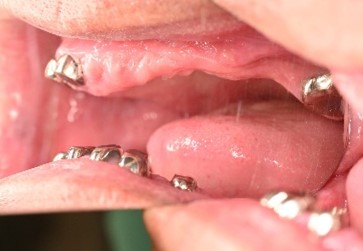

【義歯を外したところ】

【マグネット式総入れ歯】

上顎

下顎